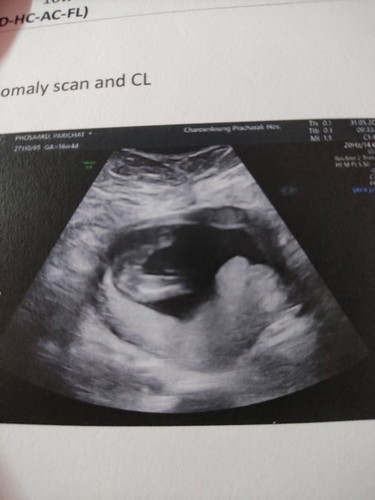

16วีค อยากถามแม่ๆว่าเป็นหญิงหรือชายคะ

อยากถามแม่ๆว่าน้องเป็นหญิงหรือชายคะ พอดีท้องแรกคลอดก่อนกำหนด ท้องนี้เลยโดนฉีดยากันคลอดก่อนกำหนดทุกอาทิตย์จนถึงท้อง8เดือนเลย

ผู้หญิงค่ะ ถ้าผู้ชายไข่จะกลมกว่านี้

น่าจะหญิงนะคะ เหมือนเห็นแคมน้อง

เเม่ ว่า ญ น้ะค่ะ เพราะเเบนเลย5555

น่าจะผู้หญิงนะคะ

น่าจะสาวนะคะแม่

กลีบชัดมากแม่